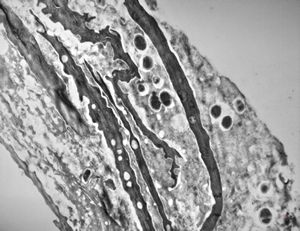

F, 39y. | collagenous and elastin fibers from corium

F,68y. | collagenous and elastin fibers from corium

M, 3y. | cutaneous nerve